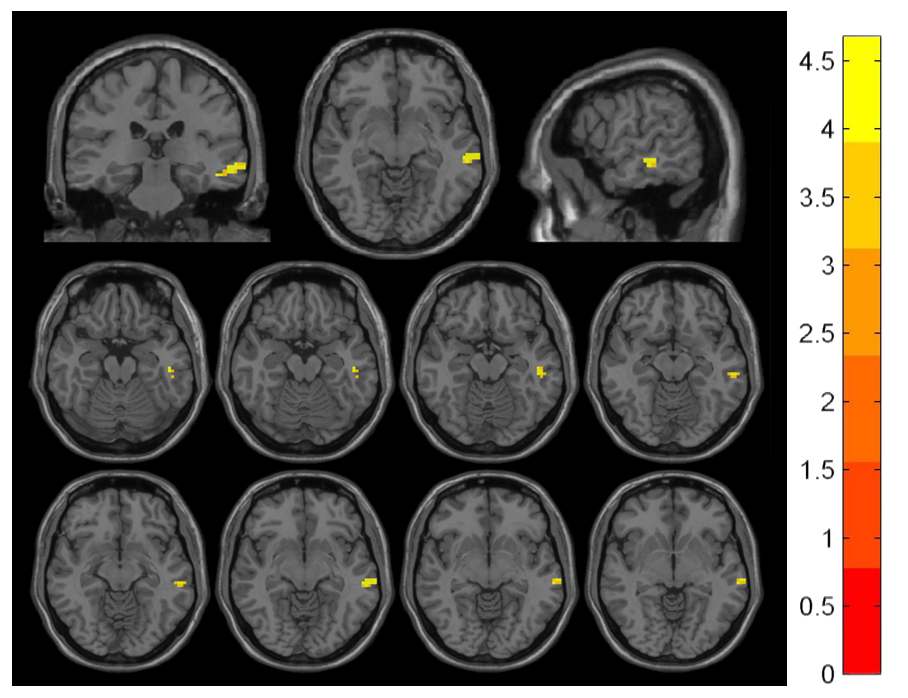

The altered brain regions in patients with chronic pain before and after stimulation included postcentral and precentral gyrus (P<0.001)[figure2], while in patients with no pain only included the middle temporal gyrus (P<0.001)[figure3].

ReHo Changes in No Pain Group Pre/Post-Stimulation